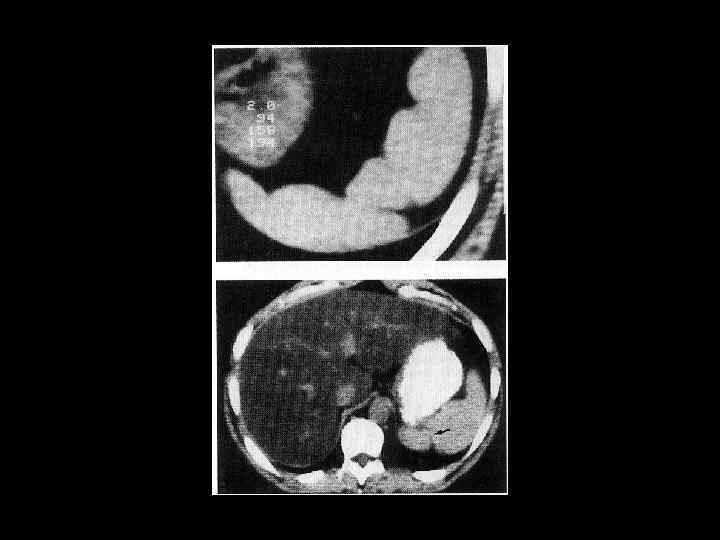

АКТУАЛЬНЫЕ ВОПРОСЫ РЕНТГЕНОЛОГИИ ЛУЧЕВАЯ ДИАГНОСТИКА ЗАБОЛЕВАНИЙ СЕЛЕЗЕНКИ Кисты и абсцессы селезенки

АКТУАЛЬНЫЕ ВОПРОСЫ РЕНТГЕНОЛОГИИ ЛУЧЕВАЯ ДИАГНОСТИКА ЗАБОЛЕВАНИЙ СЕЛЕЗЕНКИ Опухолевое поражение селезенки